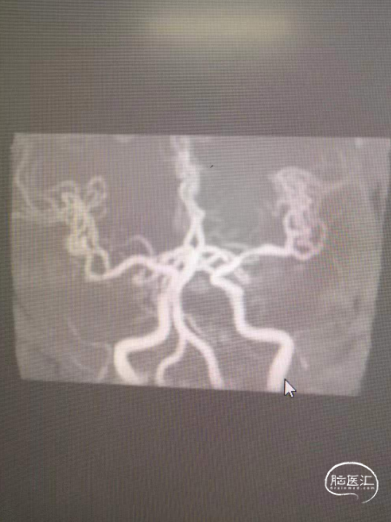

符合脑内多发缺血变性灶、梗死灶(左侧大脑半球大面积急性梗死)、软化灶T2-FLAIR/DWI表现;

符合颅脑动脉硬化并多发狭窄MRA表现,左侧颈内动脉颅内段、大脑中动脉及分支未见显示,考虑闭塞或重度狭窄,建议CTA进一步检查。

术后颈内动脉末端血流通常,左侧大脑前动脉和大脑中动脉显影正常。